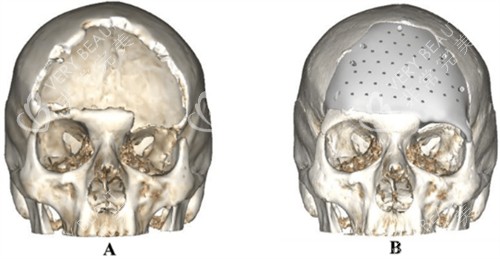

比如颅骨缺损的面积大小、部位形状不同,需要对 PEEK 材料进行个性化切割、塑形,工艺复杂度越高,相关的加工成本就会增加,更终整体费用也会随之变化。

首要考虑的是材料的适配性。

不同患者的颅骨缺损情况不同,材料的厚度、形状是否能更准一些匹配缺损部位,直接影响术后结果和舒适度。